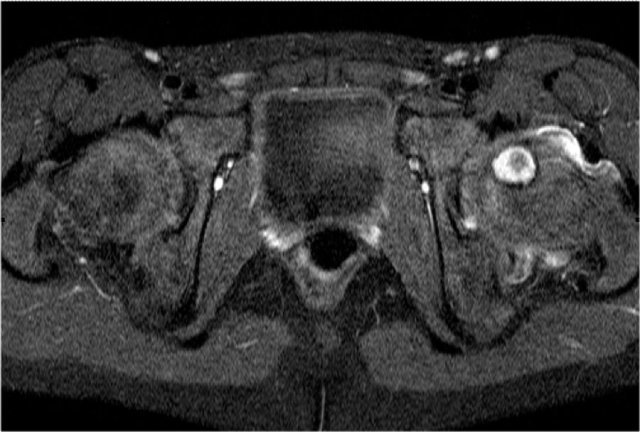

On MRI osteomyelitis appears as an area of T2 increased signal in the metaphysis with enhancement and surrounding edema in the soft tissues, and occasionally a subperiosteal abscess.

In infants and children with closed growth plates, the growth plate does not act as a barrier and infection may spread to the epiphysis and joint.

On MRI the lesion is hyperintense on T2WI. There is joint effusion and only minimal edema in the surrounding musculature.